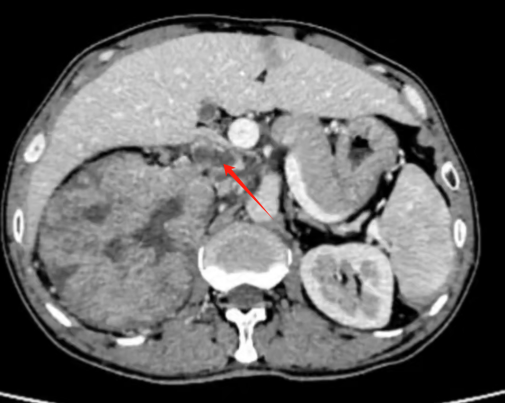

在泌尿外科领域,肾癌合并静脉瘤栓手术无疑是一块难啃的“硬骨头”:术中需要直面人体最粗壮血管的暴露、切开以及精细缝合等诸多棘手环节,每一步操作都如同在悬崖峭壁上行走,稍有不慎,便可能引发严重后果。

借助先进的达芬奇机器人技术,付德来团队配合得天衣无缝,仅耗时1小时,就干净利落地完成了肿瘤和瘤栓的精准切除,将术中出血量稳稳控制在200-300mL。

二附院泌尿外科团队在肾癌伴癌栓手术治疗方面积累了丰富经验,10余年前就开展了四级癌栓手术(癌栓从肾静脉延伸至右心房)。既往肾癌伴癌栓手术大部分为开放手术,创伤大、出血多,患者恢复慢,达芬奇手术机器人让癌栓手术变得更加微创和精准。近年来二附院累计完成机器人肾癌伴癌栓手术50余例,完成手术数量和质量均居西北前列。

作为肾肿瘤亚专业组带头人,付德来副主任医师谈到,在肾癌合并静脉瘤栓的手术领域,机器人技术展现出了极为显著的优势。其配备的超高清裸眼3D镜头,拥有高达10倍的放大效能,能够将组织内部的细微结构清晰地呈现于术者眼前。不仅如此,机器人所独具的机械臂结构更是一大亮点,既稳定可靠,又具备超乎寻常的灵活性,面对复杂的人体解剖结构,它能够游刃有余地实现精细解剖操作,精准抵达那些传统手术器械难以企及的细微区域。